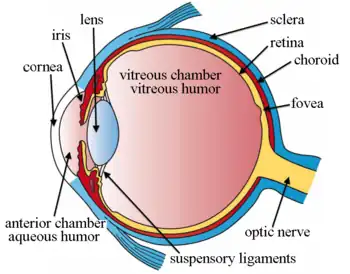

Schematic diagram of the human eye. | |

Position in the eye

The lens is located towards the front part of the vertebrate eye called the anterior segment which includes the cornea and iris positioned in front of the lens. The lens is held in place by the suspensory ligaments (Zonule of Zinn),[1] attaching the lens at its equator to the rest of the eye[2][3] through the ciliary body. Behind the lens is the jelly-like vitreous body which helps hold the lens in place. At the front of the lens is the liquid aqueous humor which bathes the lens with nutrients and other things. Land vertebrate lenses usually have an ellipsoid, biconvex shape. The front surface is less curved than the back. A human adult the lens is typically about 10mm in diameter and 4mm thick though changes shape with accommodation and size due to grow throughout a person's lifetime.[4]

Additional images

Section through the margin of the lens, showing the transition of the epithelium into the lens fibers known as the bow region. The structures of the eye labeled

The structures of the eye labeled Another view of the eye and the structures of the eye labeled